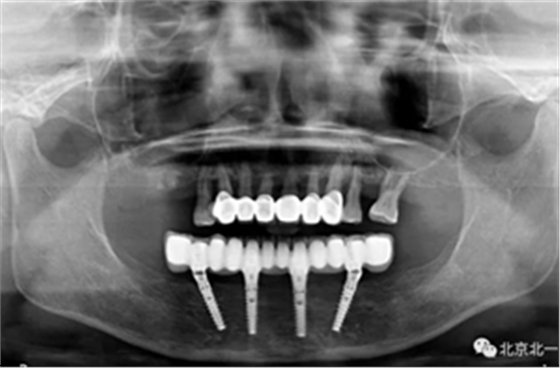

圖二十四:2017年11月復(fù)查時照片,植體很穩(wěn)定, 無骨吸收。

圖二十五:口內(nèi)照。